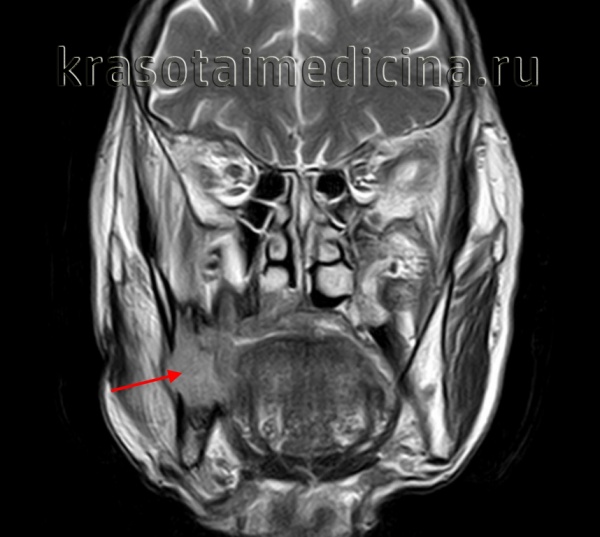

(Слева) На аксиальной МРТ (Т2 ВИ) у молодой женщины с пальпируемым образованием в поднижнечелюстной области в левой ПНЖ визуализируется хорошо отграниченная опухоль овальной формы с гиперинтенсивным сигналом. Признаки распространения опухоли за пределы ПНЖ отсутствуют.

(Справа) На цветовой допплеровской сонограмме у этой же пациентки в левой ПНЖ визуализируется хорошо отграниченное солидное образование, деформирующее наружный контур железы. В образовании не определяются кальцинаты или кистозные изменения, присутствует периферический и внутренний кровоток.

(Слева) МРТ Т2ВИ, аксиальная проекция, молодая пациентка с пальпируемым образованием в поднижнечелюстной области. В левой поднижнечелюстной железе видно гиперинтенсивное образование овальной формы. Признаков распространения за пределы железы нет.

(Справа) Допплеровское УЗИ, продольная косая проекция, эта же пациентка. Солидное образование с четкими контурами в левой поднижнечелюстной железе. Контуры железы деформированы. Кальцификатов или кист в толще железы нет. На периферии и в центре опухоли кровоток сохранен.